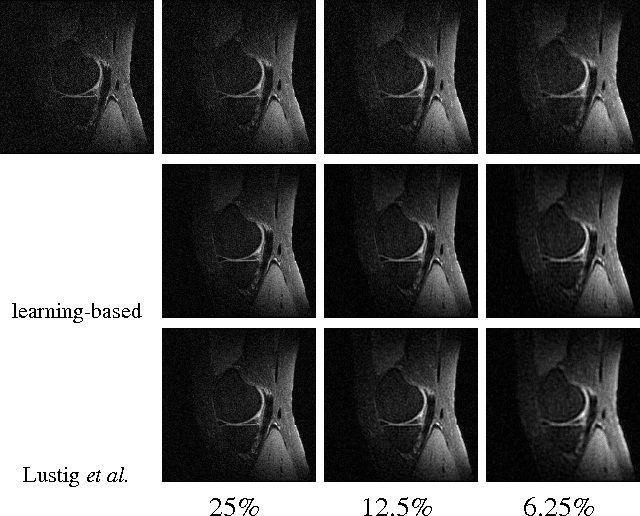

Abstract:In the area of magnetic resonance imaging (MRI), an extensive range of non-linear reconstruction algorithms have been proposed that can be used with general Fourier subsampling patterns. However, the design of these subsampling patterns has typically been considered in isolation from the reconstruction rule and the anatomy under consideration. In this paper, we propose a learning-based framework for optimizing MRI subsampling patterns for a specific reconstruction rule and anatomy, considering both the noiseless and noisy settings. Our learning algorithm has access to a representative set of training signals, and searches for a sampling pattern that performs well on average for the signals in this set. We present a novel parameter-free greedy mask selection method, and show it to be effective for a variety of reconstruction rules and performance metrics. Moreover we also support our numerical findings by providing a rigorous justification of our framework via statistical learning theory.

Abstract:The standard approach to compressive sampling considers recovering an unknown deterministic signal with certain known structure, and designing the sub-sampling pattern and recovery algorithm based on the known structure. This approach requires looking for a good representation that reveals the signal structure, and solving a non-smooth convex minimization problem (e.g., basis pursuit). In this paper, another approach is considered: We learn a good sub-sampling pattern based on available training signals, without knowing the signal structure in advance, and reconstruct an accordingly sub-sampled signal by computationally much cheaper linear reconstruction. We provide a theoretical guarantee on the recovery error, and show via experiments on real-world MRI data the effectiveness of the proposed compressive MRI scheme.